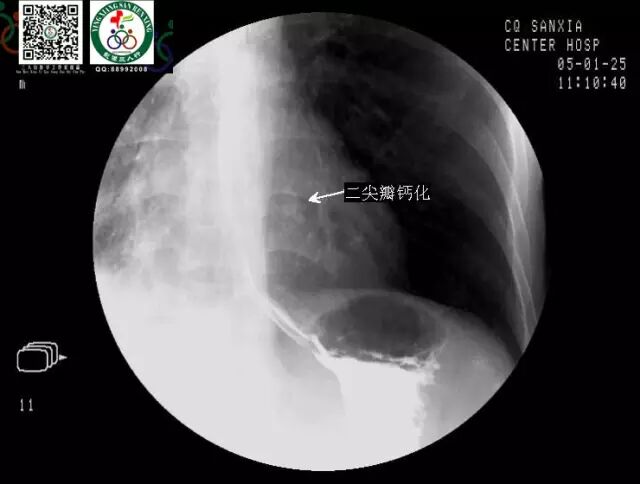

钡餐检查食道阴影